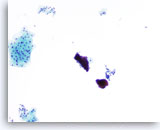

Lubricant C treated vial

…shows the lubricant staining a deep purple and resembling dense mucoid material in appearance. In this instance, the specimen had very scant cellularity and fragments of lubricant obscuring the epithelial cells. The decreased cellularity was most likely the result of excessive lubricant interfering with cell collection during slide preparation.

10x

Lubricant C treated vial

…shows the lubricant staining a deep purple and resembling dense mucoid material in appearance. In this instance, the specimen had very scant cellularity and fragments of lubricant obscuring the epithelial cells. The decreased cellularity was most likely the result of excessive lubricant interfering with cell collection during slide preparation.

10x